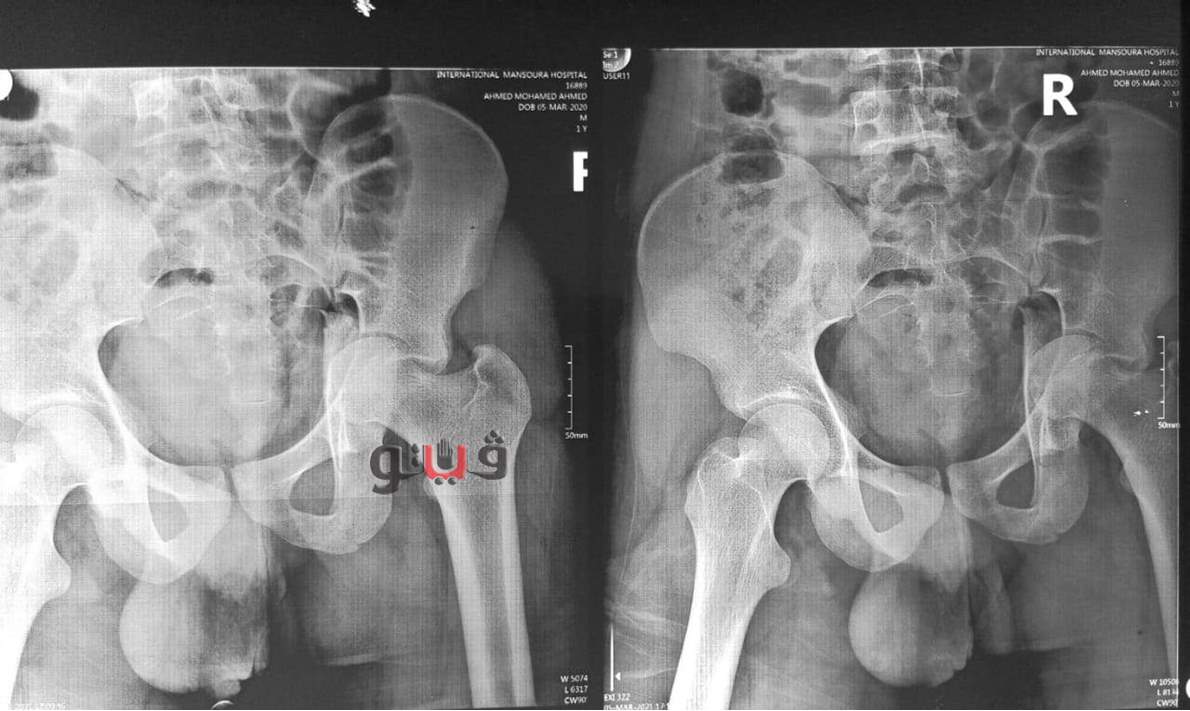

أعلن الدكتور سعد مكي وكيل وزارة الصحة بالدقهلية عن نجاح فريق طبي في إنهاء معاناة شاب يبلغ من العمر 20 عاما كان يعاني من كسر بحق مفصل الفخذ الأيسر مع خلع بالمفصل مع تأثر العصب الوركي وتمكن الفريق الطبي من إجراء جراحة عاجلة لرد الخلع وتثبيت الكسر بشرائح ومسامير معدنية وعمل استكشاف للعصب الوركي.